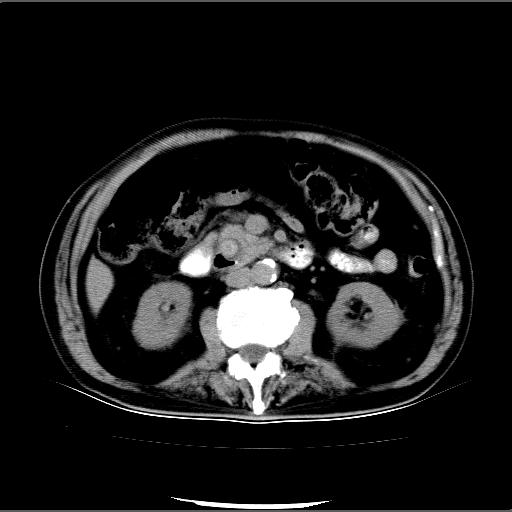

患者男82岁,黄染,发热10天,无腹痛。

1胆总管下端结石伴肝内外胆管扩张;2胆囊颈部结石伴胆囊积液

胆囊多发结石,胆囊积液;胆总管中下段结石,中上段扩张。

胆总管下段结石伴胆道系统扩张;胆囊炎伴胆囊结石.

1、胆总管壶腹部结石并胆总管、胆囊及肝内胆管扩张。2、胆囊多发结石。3、两下胸膜局限性增厚。4、胃体部大弯侧胃壁稍厚,建议:多量饮水后增强ct扫描除外占位性病变。

此病例有结果了:患者术后为:胆总管下段结石伴胆道系统扩张;胆囊炎伴胆囊结石。

各位战友分析的都很正确,是一个典型的病例。